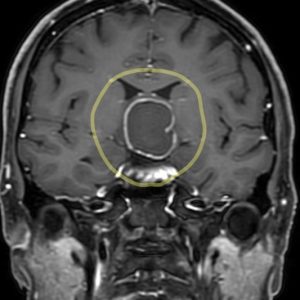

この方は、数ヶ月前からのひどい頭痛と両眼の視力障害で、仕事に支障を来すようになり病院を受診され、MRIにて頭蓋咽頭腫と診断されました。

黄色で示した所に4-5センチ径の頭蓋咽頭腫を認めます(図1、図2)。脳の正中で、視神経や視床下部、内頚動脈などの重要構造物に囲まれたところに腫瘍が発生しています。眼科での検査では軽度の視野障害が認められ、言語聴覚士による高次脳機能評価では高次脳機能障害は認めないとの所見でした。糖尿病・内分泌内科でのホルモン検査では、成長ホルモン、性ホルモンなどの内分泌障害を認めました。